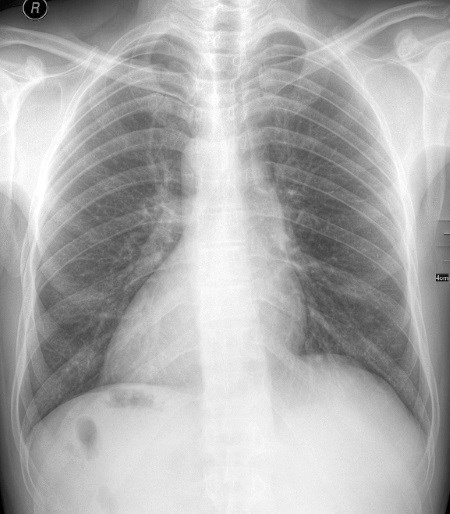

Клинические проявления Незначительные анатомические аномалии в основном совместимы с жизнью. Если такие изменения не слишком очевидны, то их случайно обнаруживают при медицинском осмотре на предмет, не связанный с отклонением, либо в процессе вскрытия. Анатомические аномалии интригуют медицинский мир, ведь их эмбриологическая составляющая дает представление о том, как развивается человеческое тело. ![]() Форма ушей так же уникальна, как и отпечатки пальцев. Чаще всего аномалии развиваются в сосудистых структурах, особенно в артериях. Например, в некоторых артериях присутствует дополнительная ветвь или же ниспадающие ветви могут раздваиваться в неожиданных местах. В норме седалищный нерв раздваивается в средней части бедра, но это может случиться и в ягодичной области. Такие аномалии вызывают клинические трудности и проблемы всякий раз, когда дело доходит до проведения стандартных процедур или сложных операций. В частности, для безопасности пациента хирург должен знать о возможных изменениях в ветвлении коронарной артерии или структур из Виллизиева круга. Поэтому очень важно использовать различные методики визуализации, которые смогли бы выявить все возможные аномалии до проведения операций. К сожалению, не все вариации можно визуализировать, и зачастую это приводит к серьезным хирургическим осложнениям. Определение анатомических вариаций нужно не только для подбора хирургической методики. Такие вариации способны влиять на степень выраженности различных симптомов и увеличивать риск развития определенных заболеваний либо обусловливать их течение. Следовательно, медицинские специалисты должны практиковаться и учиться на различных вариациях тела человека. В этом им помогают опыт препарирования, использование передовых технологий визуализации и клинической диагностики, а также коллективная работа. Добавочные структуры Наличие дополнительной части тела, которая отличается от общей структуры, – это куда более распространенное отклонение, чем нам кажется. Оно возникает, когда зигота начинает расщепляться, но не может правильно завершить этот процесс. По той же причине появляются сиамские близнецы. Участок, в котором началось расщепление, и будет определять, какая часть тела частично или полностью продублируется. Добавочные структуры могут возникать в любой системе органов. ![]() Подковообразные почки Некоторые люди рождаются с дополнительной почкой или мочеточником. Но у небольшого процента населения обнаруживают подковообразную почку, которая появляется в результате сращения нижних долей обоих почек. Подковообразная почка довольно редко бывает связана с различными патологиями; в обычных случаях она существует бессимптомно. Такие вариации имеют особое значение в трансплантологии, поскольку в этом процессе важно учитывать любые анатомические вариации. ![]() Дополнительный палец при полидактилии обычно менее развит, чем остальные. Длинная ладонная мышца В предплечье расположена самая уникальная мышца человека. Она есть не у всех, а у некоторых такая мышца присутствует лишь в одной руке. Длинную ладонную мышцу можно вычислить по сухожилию, которое проступает по центру на внутренней стороне запястья, если напрячь руку и сжать кулак. Отсутствие этой мышцы не влияет на работу руки или силу захвата. Однако при наличии она станет золотым резервом в случае, если вам когда-либо понадобится пересадить кусок мышцы. ![]() Это рентгеновский снимок пациента с декстрокардией (смещением сердца вправо, а не влево). Транспозиция органов Это крайне редкая аномалия. Она характеризуется зеркальным, или обратным, расположением внутренних органов, отличающимся от общепринятого. Например, обычно сердце смещено влево. Но при транспозиции – или, в данном случае, декстрокардии – сердце смещено вправо. ![]() Длинная ладонная мышца есть не у всех. Ее сухожилие можно увидеть, если сжать руку в кулак. Слова благодарности В первую очередь я хотел бы поблагодарить профессора, кавалерственную даму Сью Блэк, проректора по работе со студентами из Университета Ланкастера, за то, что она любезно согласилась потратить время на рассказ о ряде аспектов анатомии и своих текущих проектах. Также я бы хотел поблагодарить доктора Басаама Аведа (консультанта по лечению инсультов в фонде госпиталей Хиллингтона и главного врача в Университете Брунеля) за рецензирование части главы по нервной системе и за то, что познакомил меня с профессором Барри Митчеллом (почетным профессором валеологии в «Науках здравоохранения» Университета Де Монфор и бывшим руководителем отдела анатомии в Медицинской школе Саутгемптонского университета), который просмотрел эту книгу. Я бесконечно благодарен за вашу помощь. Отдельно я хотел бы поблагодарить мою замечательную супругу Никки Доу за ее непоколебимую поддержку в процессе написания книги, терпение, вдохновение и понимание (ты была моей опорой) и мою дочь Элоди за то, что мирилась с нехваткой нашего совместного досуга. Кроме того, выражаю благодарность моим замечательным братьям и сестрам Джо, Вив, Джеффу и Джен за их терпение и безоговорочную поддержку, моей тете Мейбл за то, что стала мне второй мамой, и всей моей большой семье в Лондоне и Дорсете. И, наконец, от всего сердца благодарю всех друзей, которые не переставали верить в меня и подбадривали на всех этапах. Я бы хотел посвятить эту книгу моим покойным родителям, по которым скучаю каждый день. Элизабет Окона-Менса и Куаси Биллингс Окона-Менса, без которых всего этого бы не получилось. |